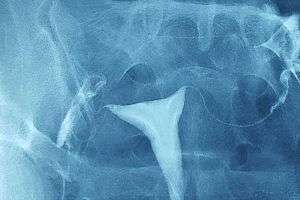

Tüplerde Sıvı Birikmesi

Bilateral Hidrosalpinks